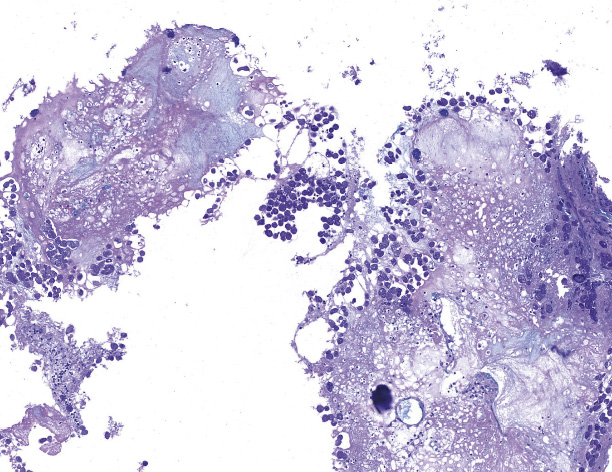

Гистологическое исследование биоптатов: фрагменты слизистой оболочки толстой кишки, замещенные преимущественно гнойно-некротическим детритом, с наличием среди детрита множества макрофагоподобных структур овальной и овоидной формы с гранулированной эозинофильной цитоплазмой, с наличием округлых ядер, смещенных на периферию, железы слизистой оболочки сохранны только в базальном отделе, с резким уменьшением количества бокаловидных клеток и клеток Панета, с умеренно выраженным ядерным полиморфизмом (рис. 2). Заключение: эрозивно-язвенный колит, наиболее вероятно – амебиазной этиологии (E. histolytica). Пациентка консультирована инфекционистом, по заключению которого неспецифичность эндоскопических изменений нуждалась в уточнении. При дополнительном обследовании бактериологические и серологические тесты не выявили кишечных инфекций (Salmonella spp., Shigella spp., anti-Y. pseudotuberculosis, anti-Y. enterocolitica, anti-Salmonella A, B, C1, C2, D, E, anti-Shigella flexneri I–V, anti-Shigella sonnei). Токсины А и В Clostridium difficile, а также простейшие в кале не обнаружены. Антитела класса IgG к амебам от 10.06.2021: 94,908 у.е. (референсные значения 0–9 у.е.). Гистологический препарат пересмотрен в июне 2021 г. в клинико-диагностической лаборатории Института медицинской паразитологии, тропических и трансмиссивных заболеваний имени Е.И. Марциновского: обнаружена Entamoeba histolytica.

Рис. 2. Гистологическое исследование препарата из язвы купола слепой кишки: скопления трофозоитов E. histolytica. Окраска альциановым синим и ШИК-реакция (PAS); × 400